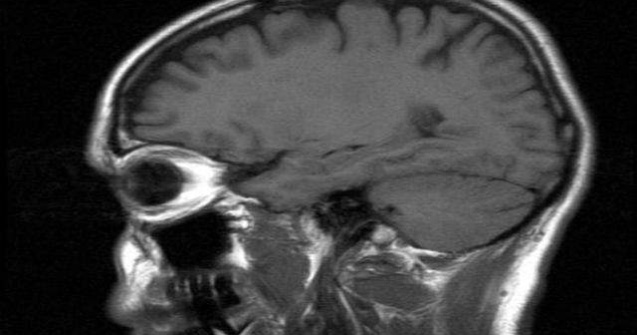

Cercetatorii britanici au descoperit un mecanism cerebral despre care cred ca ar controla dorinta de alimente bogate in glucoza.